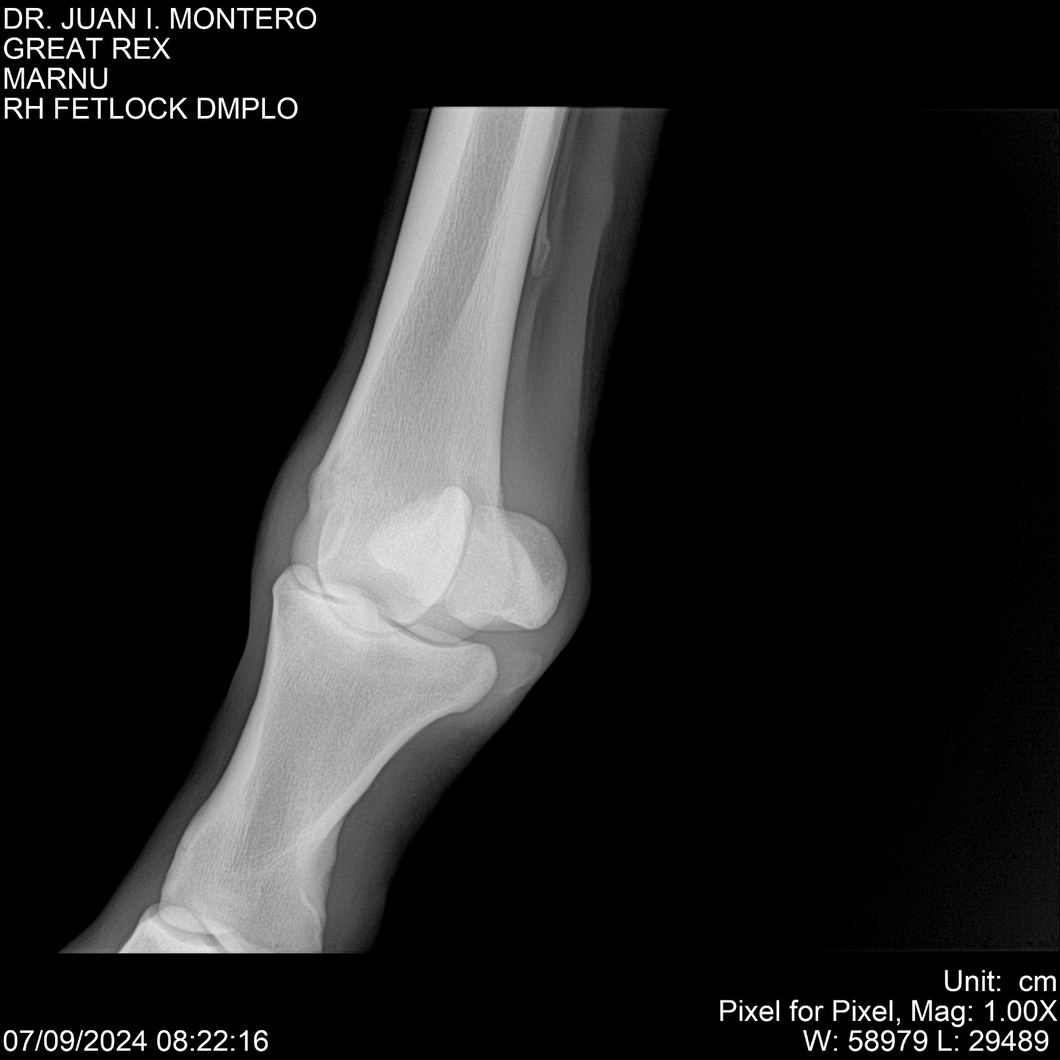

LOTE 4, GREAT REX Lote Anterior Volver al remate Lote Siguiente Ficha Contacto Montevideo - Ficha del Lote Identificador: #282518 Categoría: Yeguarizos Montevideo - 66 Visualizaciones ClicData Contacto Empresa: Abelenda N. R., Walter Hugo Nombre*: Teléfono* : E-mail* : Mensaje Enviar Registrese gratis Este contenido Exclusivo está disponible sólo para usuarios registrados Ingresar